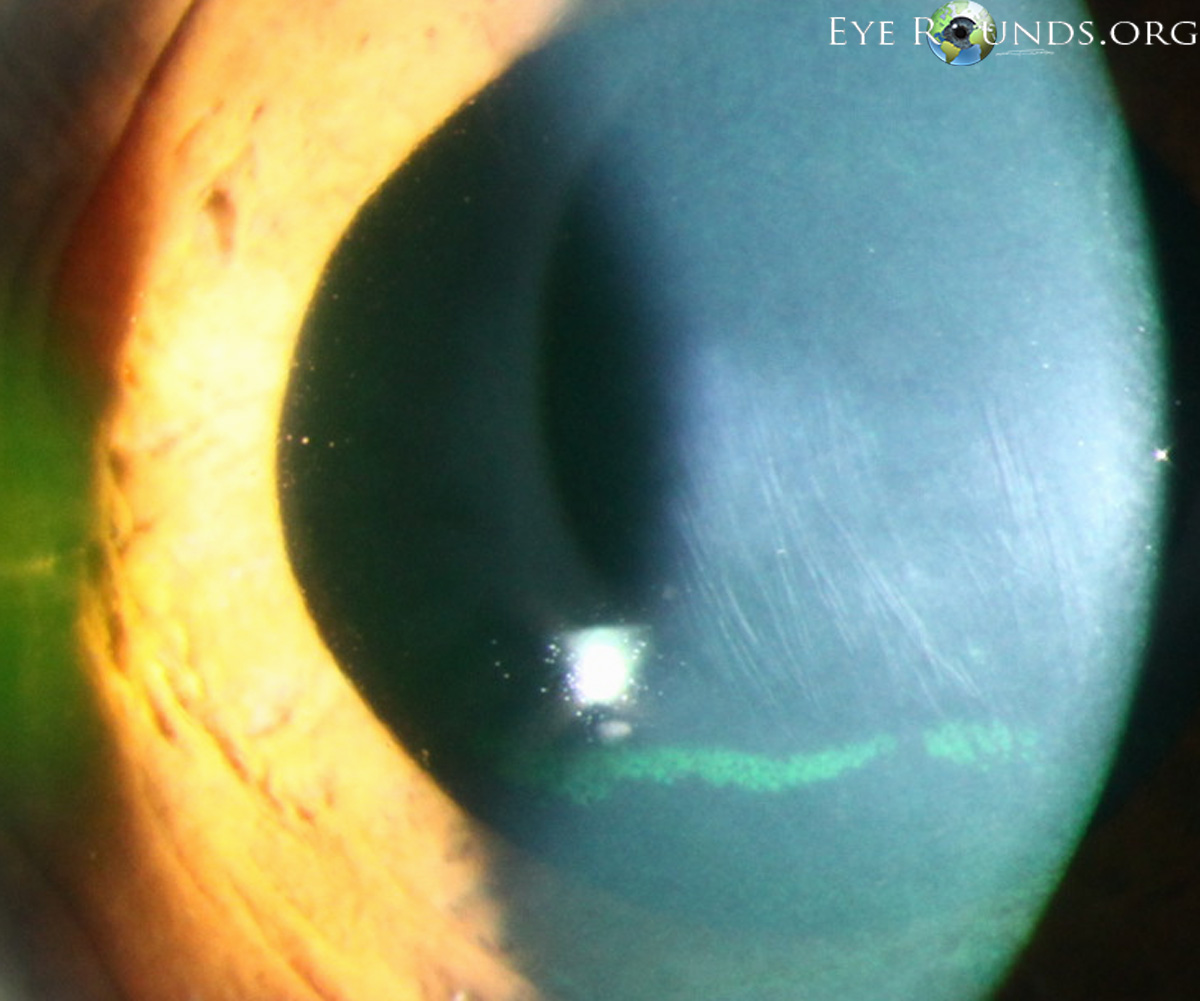

Fleischer Ring이란, 튀어나온 원추부분을 둘러싸고 철분이 각막에 침착되는 것입니다.

원추의 바닥부에 원추바닥의 가장자리를 따라서 흔히 관찰되는데,

부분적인 혹은 완전한 원형의 선이 나타납니다.

원추 주변부경계의 지표가되는데,

바닥상피에 침착된 혈철소(hemosiderin)으로 인해서 형성된것으로,

돌출이 질행될수록 점점더 고리는 더 진하게 침착되면서, 가늘어지고, 완전한 원형을 이루게됩니다.

Vogt's Striae는 각막이 얇아지면서, 돌출되면서, 발생하는 기질의 긴장선, stress line 입니다.

데스메막 바로 앞쪽에 존재하는 각막 기질에 있는 여러개의 수직선입니다.

이는 각막이 흐물흐물해지면서 발생하게되는 선으로, 안압이 가해지면 사라집니다.

각막수종 Keratoconus Hydrops 라는것은

각막의 Descemet 막 파열로 인해 전방에서부터 수분이 각막기질로 유입되면서 갑작스럽게 각막이 뿌옇게되는 현상을 의미합니다.

데스메막이 늘어나다보니 파열되면서 그 틈을 통해 방수가 기질에 들어가 기질 부종이 생기게되면,